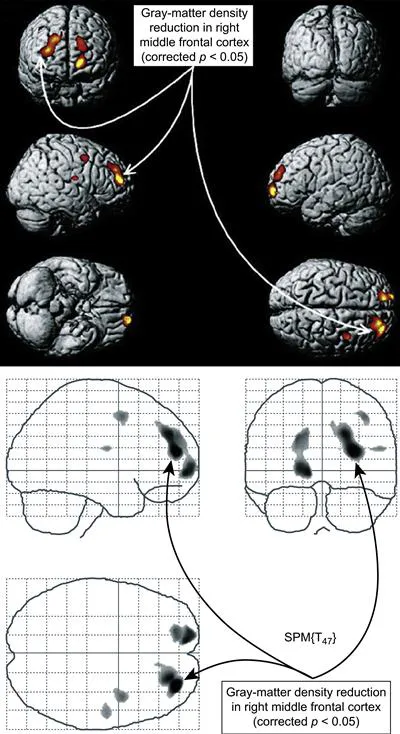

Pertaining to the abuse of stimulants, Kim and colleagues (Kim et al., 2006) documented a reduction in the gray-matter density in the right middle frontal cortex of abstinent methamphetamine abusers (Figure 1). A lower density correlated with a worse performance on a test that measures a personās ability to switch mental gears (Wisconsin Card Sorting Task). Gray matter was closer to normal in individuals who had been abstinent for >6 months than in others with a shorter period of abstinence.

Figure 1 MRI: methamphetamine reduces gray matter. The yellow and red area in the central brain view indicates a reduced gray-matter density in the right middle frontal cortex. The same deficit is shown from other perspectives in the flanking views. Reprinted with permission from Kim et al. (2006).